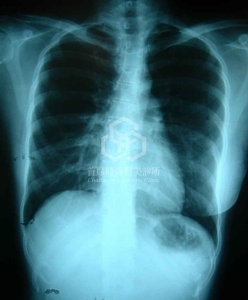

Case 3

左圖: 未婚女性, 右邊乳房幾乎沒有, 完全貼平! 屬於皮膚較緊, 無延展性的乳房(nulliparous envelope), 加上不對稱的相當嚴重, 高難度的挑戰.

右圖: 手術後三週, 經過精心設計後, 隆乳兩側義乳容積調整相差80cc, 幾乎達到對稱的目的